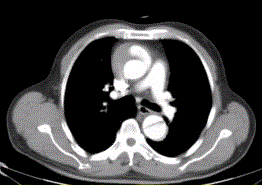

问题 患者男,67岁,高血压病史多年,自服降压药,突发胸骨后剧烈疼痛2h,服用硝酸甘油不缓解。胸透示主动脉增宽。CT影像如下图。 该例的影像学表现为

选项 A.主动脉增粗 B.主动脉内可见内膜瓣 C.真腔在左后方 D.假腔在右前方 E.假腔较小 F.升主动脉和降主动脉同时受累

答案 ABF

解析 ABF